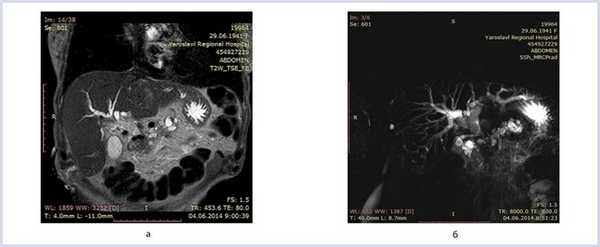

МРТ: головка поджелудочной железы — 3,3×3,5×3,8 см, тело — 2,1 см, хвост — 1,6 см, расширенный панкреатический проток — до 1,0 см, расширенный общий желчный проток — до 1,6 см, стеноз интрапанкреатической части общего желчного протока, стеноз панкреатического протока на уровне головки поджелудочной железы (рис. 1).

Рис. 1. Магнито-резонансная томография желчных протоков. а — МРТ-картина органов панкреатобилиарной зоны в Т1-режиме; б — магниторезонансная панкреатикохолангиография в Т2-режиме.

При эндоскопическом исследовании в бульбодуоденальной зоне определяется стенотическое сужение просвета двенадцатиперстной кишки (ДПК). Провести эндоскоп в нисходящую ветвь ДПК не представляется возможным.

План вмешательства: 1-й этап диагностический — эндоскопическая ультрасонография (ЭУС) и тонкоигольная пункция (ЭУС-ТИП), 2-й этап лечебный — внутреннее или наружновнутреннее дренирование желчевыводящих путей (рис. 2).